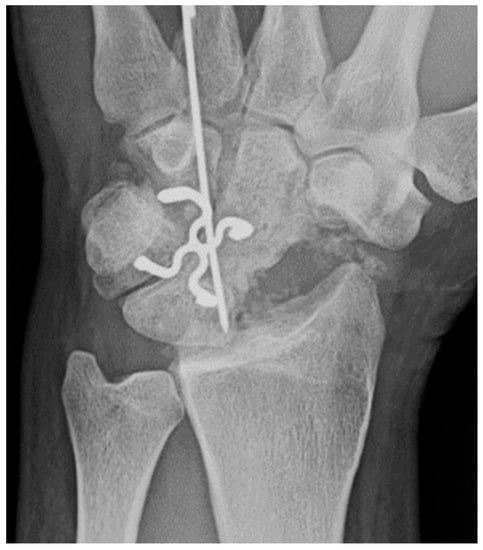

Common scaphoid fracture complications include avascular necrosis and nonunion [10]. Avascular necrosis is a dreaded outcome resulting from the loss of the proximal arterial supply due to the distal entry point of nutrient vessels. This retrograde perfusion of the proximal pole makes it vulnerable to losing its vascular supply when fractured. Sclerosis of the proximal pole indicates osteonecrosis (Figure 5). With scaphoid nonunion, biomechanical alterations contribute to rapidly progressive degenerative arthritis and instability referred to as scaphoid nonunion advanced collapse (SNAC) [16]. Nonunion occurs in 5–10% of cases and has a higher incidence in displaced fractures (Figure 6). During wrist extension, the distal scaphoid fragment rotates into flexion while the proximal scaphoid fragment extends with the lunate. The resultant abnormal contact between the distal fragment and radius begins the first stage of degenerative collapse. This progresses into the second stage as scaphocapitate osteoarthritis develops and finally to the third stage with progression to capitolunate osteoarthritis and proximal radial migration of the capitate dorsal to the lunate. Treatment of SNAC wrists, depending on the degree and severity of the osteoarthritic collapse, includes scaphoidectomy with four-corner arthrodesis or wrist fusion [17]. Four-corner fusion helps reduce joint pain while maintaining some range of motion, as opposed to total wrist fusion (Figure 7). Another option is proximal row carpectomy with resurfacing capitate pyrocarbon implant placement [18].

Figure 7. Four corner fusion with scaphoidectomy and surgical staple fusion of the lunate, capitate, hamate, and triquetrum with temporary Kirschner wire fixation.